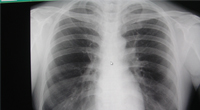

肺がんでは胸部X線など。